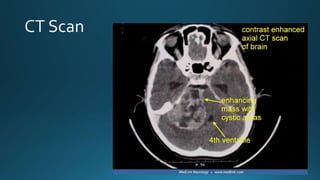

• CT scanning For patients intolerant of MRI, or

when it is contraindicated, air-

contrast CT is capable

of showing intra-canalicular

tumour.

For this, air is inserted into the

subdural space byway of a lumbar

puncture. Following

removal of cerebrospinal fluid.